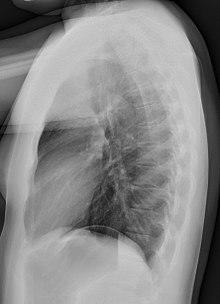

Lateral views of the chest are obtained in a similar fashion as the posteroanterior views, except in the lateral view, the patient stands with both arms raised and the left side of the chest pressed against a flat surface.

Required projections can vary by country and hospital, although an erect posteroanterior (PA) projection is typically the first preference. If this is not possible, then an anteroposterior view will be taken. Further imaging depends on local protocols which is dependent on the hospital protocols, the availability of other imaging modalities and the preference of the image interpreter. In the UK, the standard chest radiography protocol is to take an erect posteroanterior view only and a lateral one only on request by a radiologist.[5] In the US, chest radiography includes a PA and Lateral with the patient standing or sitting up. Special projections include an AP in cases where the image needs to be obtained stat and with a portable device, particularly when a patient cannot be safely positioned upright. Lateral decubitus may be used for visualization of air-fluid levels if an upright image cannot be obtained. Anteroposterior (AP) Axial Lordotic projects the clavicles above the lung fields, allowing better visualization of the apices (which is extremely useful when looking for evidence of primary tuberculosis).